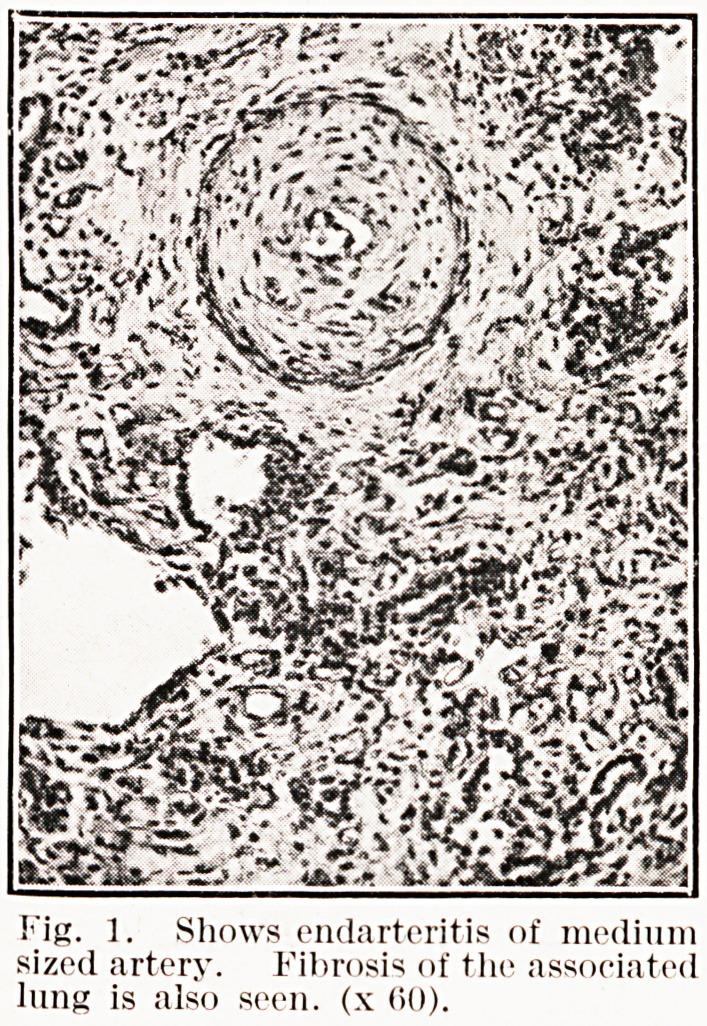

The rheumatic lung; report of two cases.

Glasgow Med J. 1947 May;28(5):127-33.